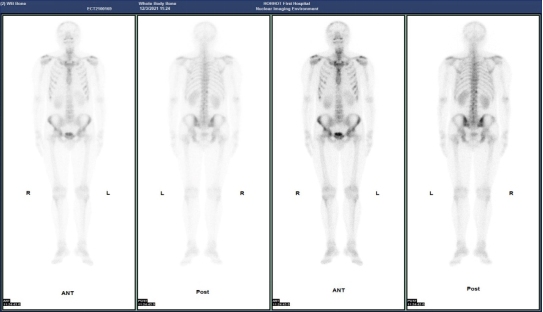

(病例二)患者,男,63岁,患者因胸憋气短、间断咳嗽咳痰就诊。门诊CT示:双肺底感染;右肺上叶占位性病变。患者今年4月份提重物时感右侧胸部拉伤,后疼痛数日。MIP图示:C6/C7椎体吻合面、右侧第7侧肋小片状放射性摄取增高,SPECT/CT示:右侧第7侧肋骨质不连续,可见骨痂形成。C6/C7椎体吻合面可见唇样骨质增生,椎体周围软组织无明显肿胀。结合病史,考虑右侧第7侧肋骨折愈合期;C6/C7椎体吻合面终板炎。

(病例三)患者,男 44岁,左肺下叶恶性肿瘤(T4N2M1c,IVB),纵膈继发性恶性肿瘤,胸膜继发性恶性肿瘤,骨和骨髓继发性恶性肿瘤。靶向药物治疗后为评估骨继发恶性肿瘤来诊。MIP图示:与2021-8-3日片比,2021-12-21日片示左侧第8后肋病灶放射性摄取明显减低,左侧第3后肋、胸骨柄片状放射性摄取范围减小,右侧第6前肋、L2椎体放射性摄取范围无明显变化。结论:与2021-8-3日片比:左侧第8后肋、左侧第3后肋、胸骨柄病灶骨盐代谢明显减低,提示肿瘤细胞活性减低;右侧第6前肋、L2椎体病灶骨盐代谢无明显变化。